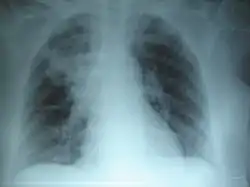

![]() ذات الرئة السفلي الأيمن: يُؤدي التليف الكيسي المُزمن إلى تدمير النسيج البرانشيمي للرئة، مُسببًا في النهاية موت المريض نتيجة لتليف الجهاز التنفسي. ذات الرئة السفلي الأيمن: يُؤدي التليف الكيسي المُزمن إلى تدمير النسيج البرانشيمي للرئة، مُسببًا في النهاية موت المريض نتيجة لتليف الجهاز التنفسي. | |